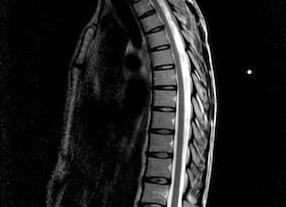

Наиболее распространенными на сегодняшний день методами с высокой точностью диагностики являются МРТ (магнитно-резонансная томография) и КТ (компьютерная томография).